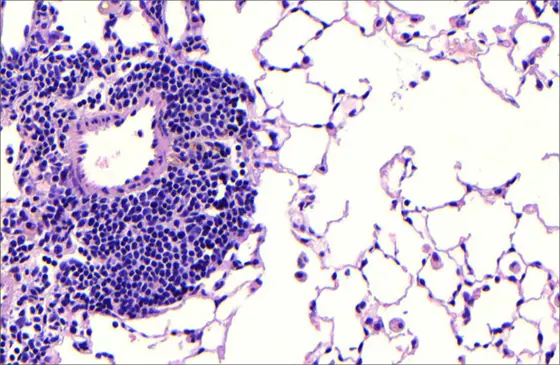

Gewebeschnitt durch die Lunge einer Maus, die über sechs Monate hinweg Zigarettenrauch ausgesetzt war. In den sich entwickelnden Follikel sind dicht gepackte Entzündungszellen zu erkennen, geschädigte Alveolarstrukturen vergrößern den Luftraum. Beides sind charakteristische Merkmale der COPD.

Tatsächlich gibt es viele Parallelen zwischen der Entstehung von Krankheiten in der Leber und in der Lunge. Bei COPD bilden Immunzellen neu organisierte Strukturen aus, sogenannte tertiäre Follikel. Von diesen weiß man, dass sie für das Fortschreiten der Krankheit relevant sind. Die Follikel können sich nur dann bilden, wenn der Lymphotoxin-Beta-Rezeptor in der Lunge aktiviert ist – also der gleiche Rezeptor, den Heikenwälder bereits in seiner Studie an der Leber blockiert hat. „Unser Ziel war es, herauszufinden, welche Funktion dieser Rezeptor und seine Signalwege bei der COPD einnehmen und ob wir sie für therapeutische Zwecke nutzen können“, sagt Yildirim. Die Forscherinnen und Forscher blockierten daher die Signalwege des Lymphotoxin-Beta-Rezeptors in den Lungen von Mäusen, die aufgrund chronischen Zigarettenrauchs COPD-typische Symptome entwickelt hatten (Immunzellfollikel, Fibrose und Zelltod von Lungenepithelzellen).